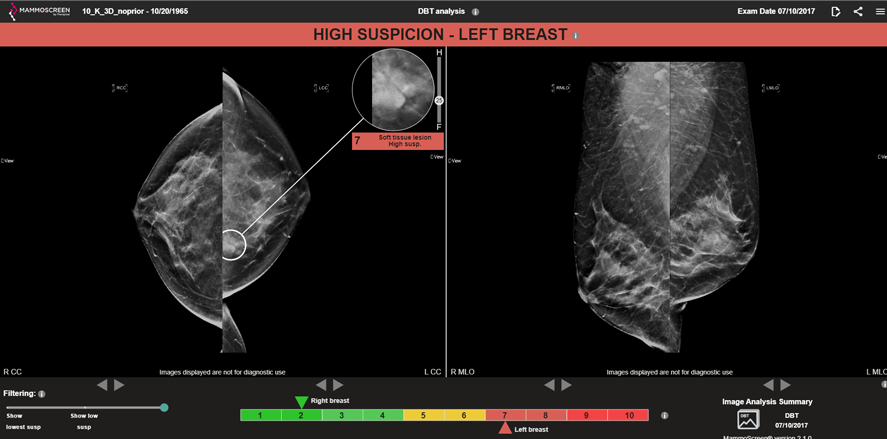

The 3D evaluation by itself was determined to an MS Score of 7.

Patient 3D Screening No PriorMS Score: 7

When the 3D evaluation took place with the prior exam, the result was a 9.

Patient 3D Screening WITH PriorMS Score: 9